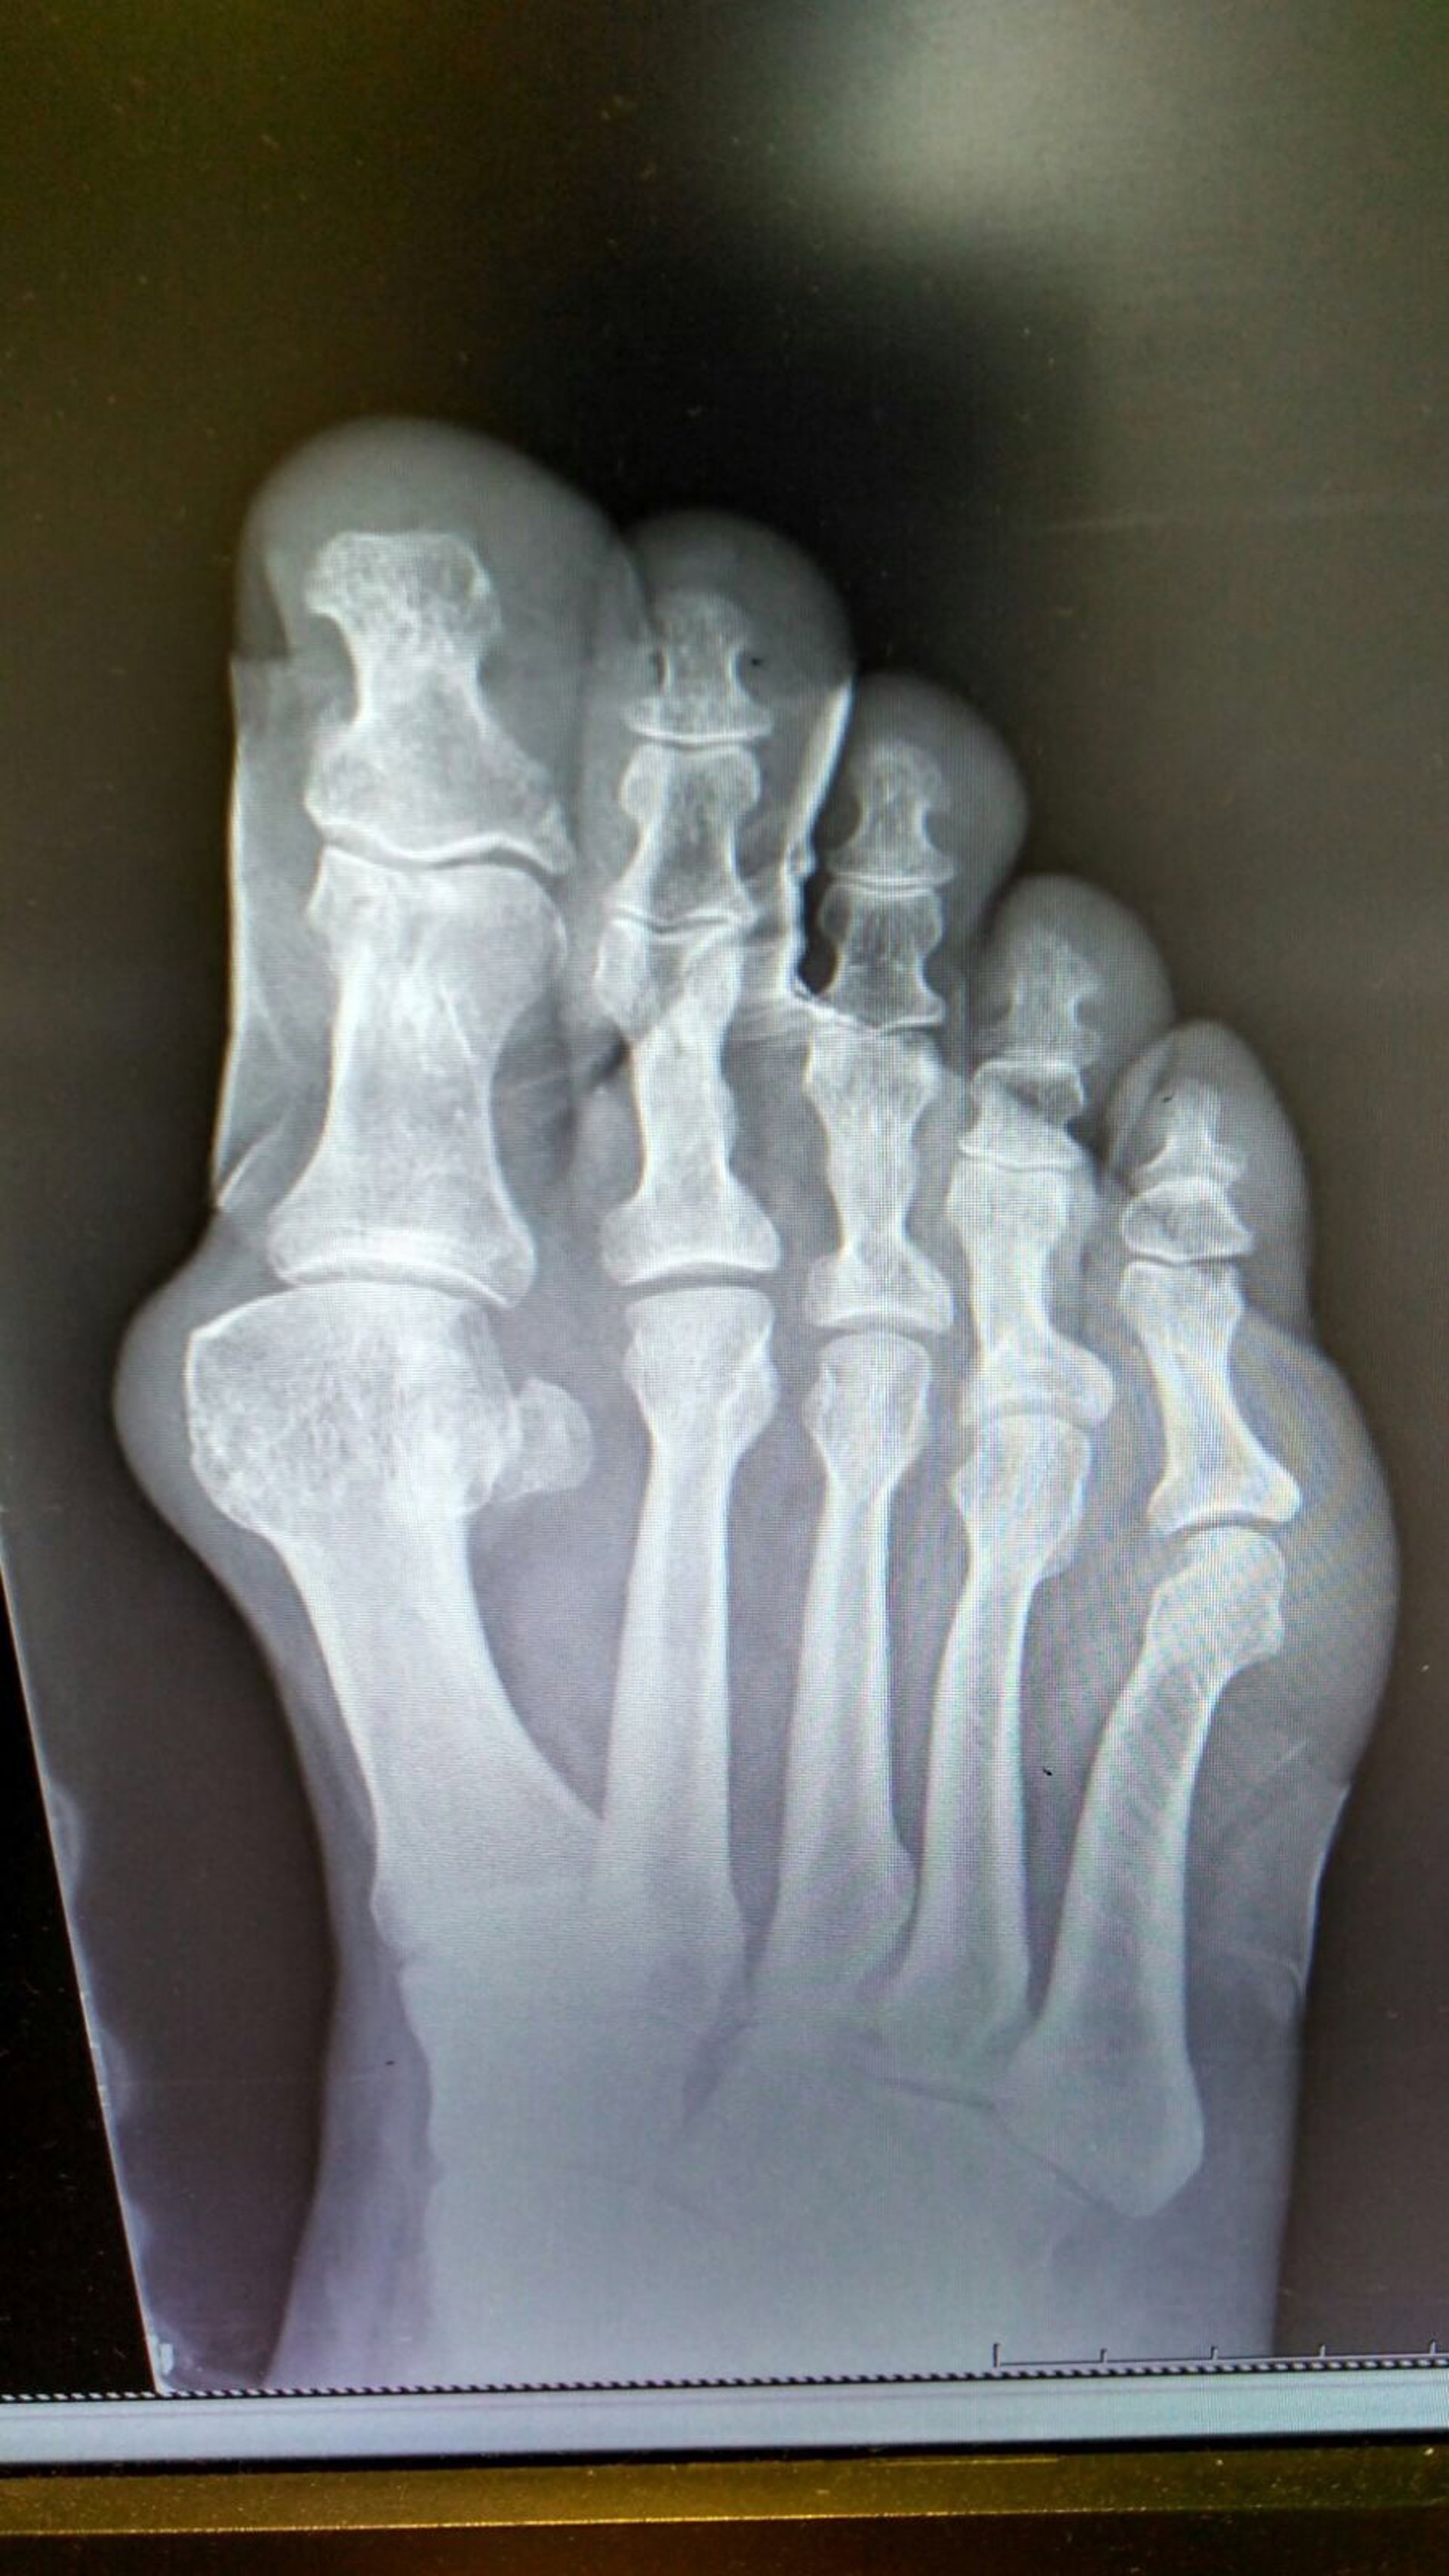

Archivo - Imagen del pie

Otras afecciones son la atrofia y el desplazamiento de la grasa plantar, que provocará unos puntos de hiperpresión sobre los huesos de la planta de los pies y generará dolor. En este caso, el tratamiento consiste en realizar un estudio biomecánico y confeccionar soportes plantares personalizados diseñados para descargar las zonas de hiperpresión.